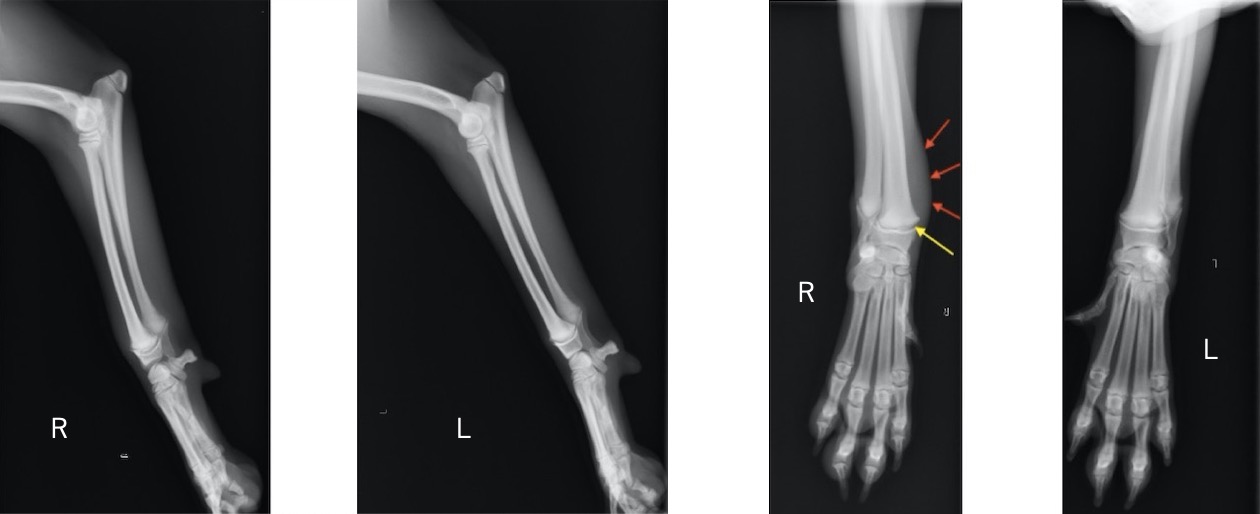

単純X線検査における四肢の成長板(矢印が成長板です)

単純X線画像検査上、側面像では大きな左右差は認められませんでしたが、背掌像にて右前肢の軟部組織の腫脹と成長板の間隙が広くなっていることから橈骨遠位成長板骨折(Salter-Haris Type1)と診断し、外科的処置を行いました。

初心時のX線画像検査初見 赤矢印:軟部組織の主張、黄矢印:橈骨遠位成長板(左前肢と比較すると、成長板の隙間が広くなっております)